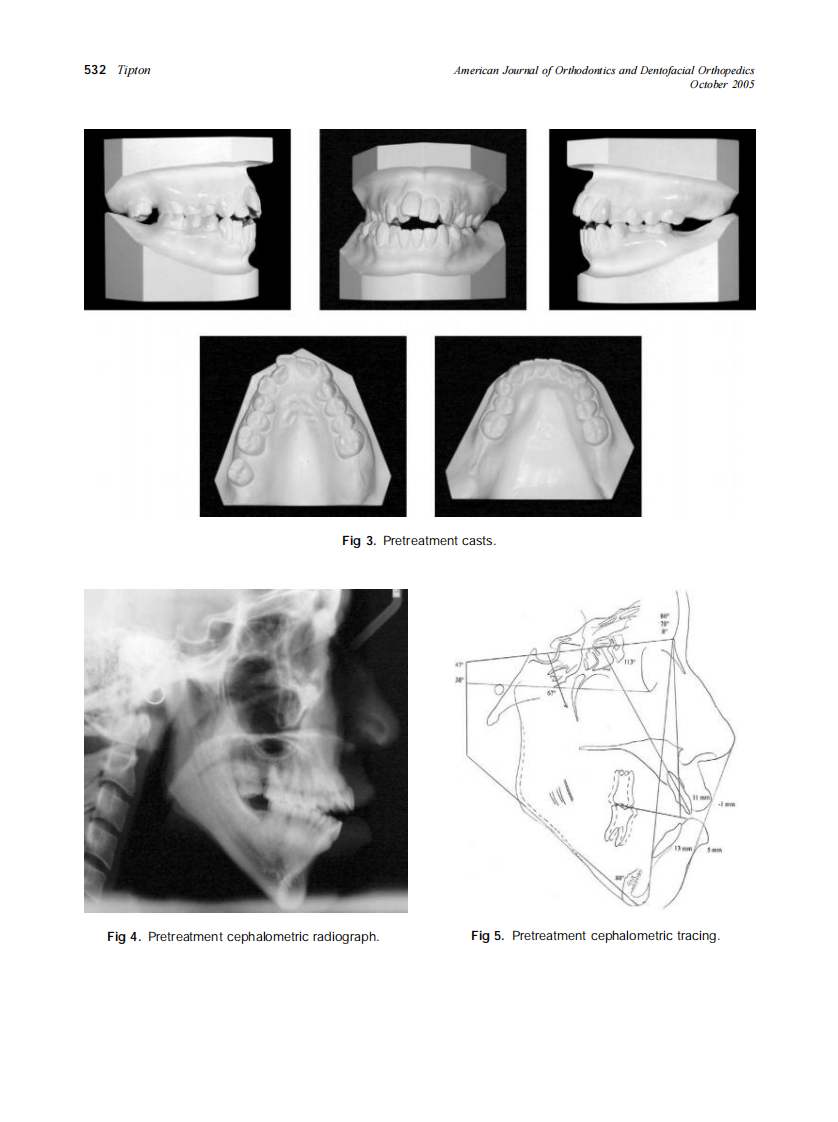

2005_128_4_528_534_Tipton.pdf